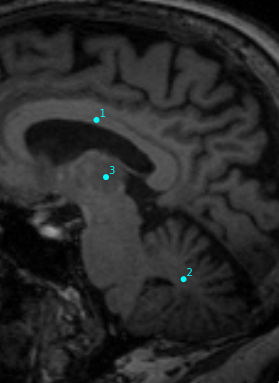

- Objectif : Comparaison de méthodes automatiques et de méthodes manuelles pour la segmentation du thalamus sur des IRM cérébrales

Circonstances : Expérience MAGNIMS

Visualisation simple d'une segmentation

Comparaison des segmentations